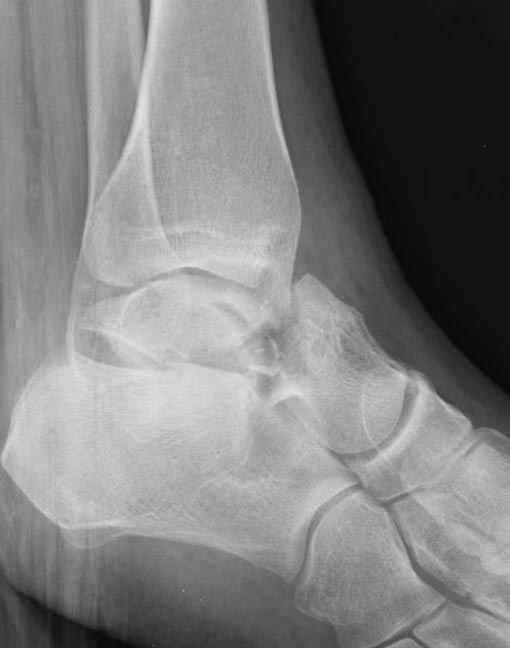

Уважаемые участники русского Ортофорума, поздравляю всех со всеми прошедшими праздниками: Новым годом, Рождеством, Hanukkah, Kwanzaa, желаю участникам всего наилучшего и здоровья.Повреждение таранной кости.Больной 81г автоавария, повреждение таранной кости, здесь снимки. Какие рекомендации?Djoldas Kuldjanov, MDDepartment of Orthopedic SurgerySt. Louis University Medical Center

Вдогонку по поводу перелома таранной кости, больная 81, не страдает диабетом, перелом закрытый, в первый же день поступления ограничились временным наружным фиксатором (как на снимке).

Планировалась открытая фиксация после спадения отека, но больная пожелала лечиться по месту жительству в другом штате..